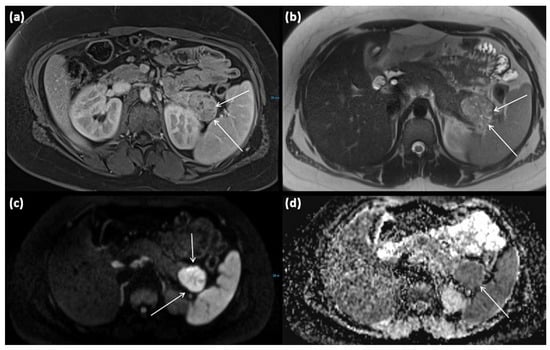

Figure 9.

MRI of a 15-year-old female patient with axial T1w after gadolinium-based contrast administration (a) T2w (b) as well as DWI (diffusion-weighted imaging) weighting ((c), b = 1000) and ADC map (apparent diffusion coefficient) (d). MRI shows a solid tumor of the pancreatic tail. In T2w, almost exclusively, intermediate to hypointense signals can be seen, showing high cellularity in the absence of cystic parts. There is a strongly hyperintense signal in DWI with a signal decrease in ADC. The tumor is marked with arrows in all sequences.